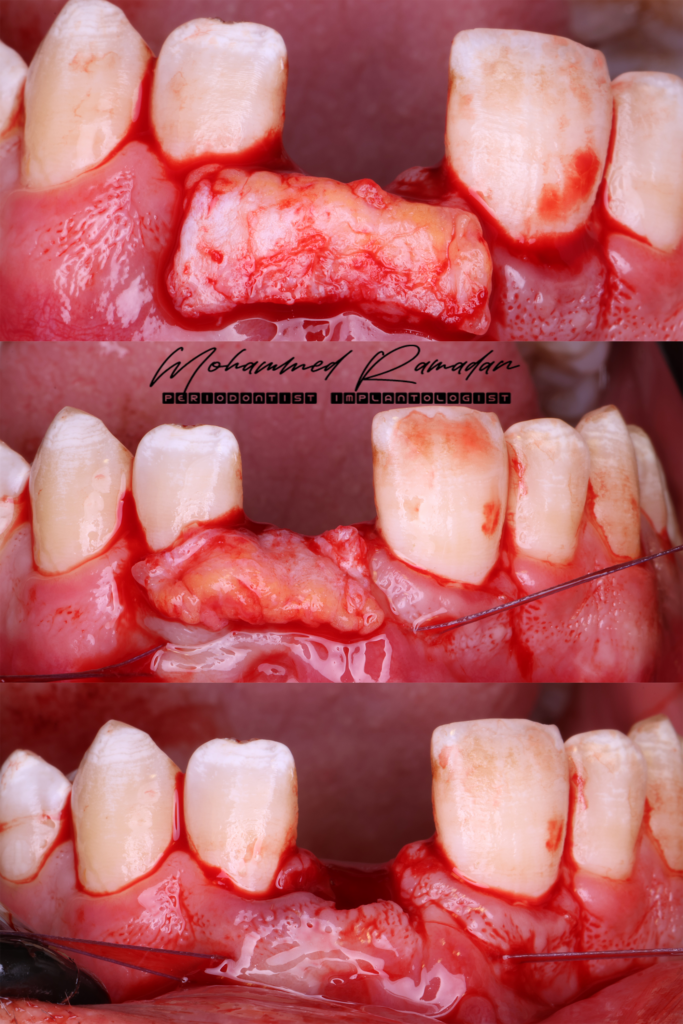

Stage One: Implant Placement and GBR

- A full-thickness mucoperiosteal flap was elevated.

- Guided osteotomy preparation was performed, followed by fully guided implant insertion.

Stage Two: Soft Tissue Management and Temporization

- Implant uncovery was performed.

- Sub-epithelial connective tissue graft (CTG) placed via tunnel approach.